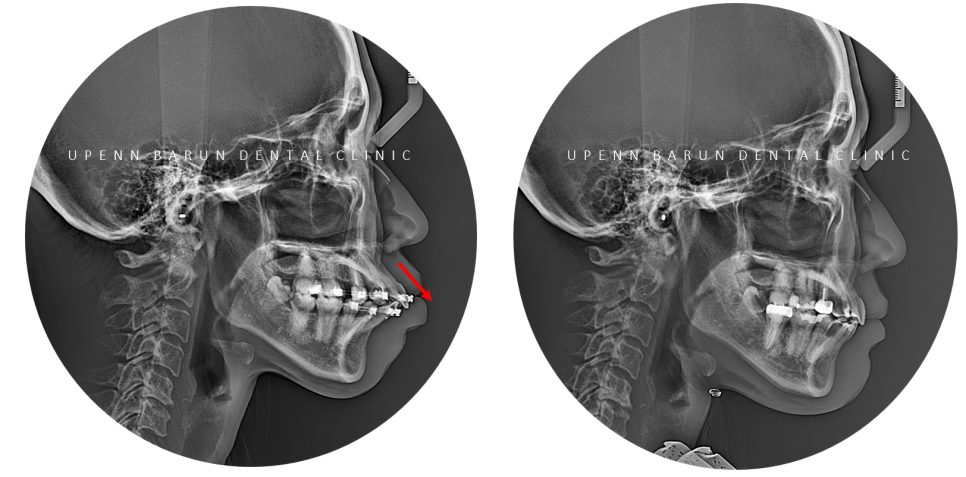

또 돌출된 치아를 개선하기 위해

미니스크류를 이용해

치아 이동을 효과적으로 도와주었습니다.

미니스크류는

비수술적 교정방법 중 하나로 통증이 많지 않고

치아의 이동이 원활해져 진료기간을 단축시키고

원하는 만큼 돌출입을 개선시킬 수 있습니다.

앞으로 돌출되어 있던 앞니의 각도가 개선되면서

치아의 기능적인 부분도 많이 개선 되었는데요,